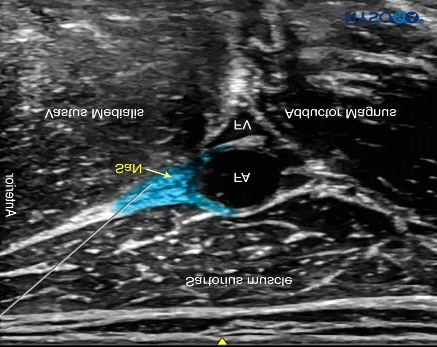

The Anaesthesiologist Team (Vibrant) at Harmony hospital utilizes USG guided Adductor Canal Block along with multimodal analgesia technique to alleviate the surgical site pain of knee arthroplasty.

For years, femoral nerve block (FNB) has been considered as the main peripheral nerve block for postoperative analgesia following knee surgery. However, quadriceps weakness as the major downside of FNB led to searching for alternative nerve blocks. In recent years, adductor canal block (ACB) has been introduced as a pure sensory nerve block for postoperative analgesia following knee surgery .